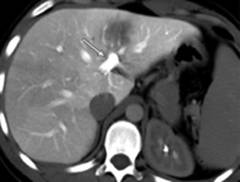

CT la o femeie de 54 de ani cu trifurcatia venei porte (tipul 2 anatomic) si cancer colorectal metastatic.

La 9% dintre pacienti, vena porta principala se trifurca în vena porta stânga (sageata dreapta subtire), vena porta anterioara dreapta (sageata dreapta groasa) si vena porta posterioara dreapta (sageata curba).